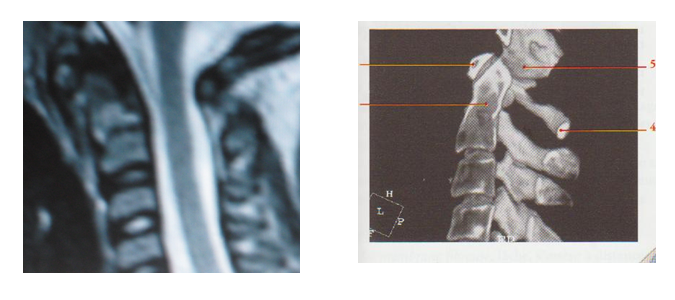

Pour lever les derniers doutes mettons en regard l’IRM et un cliché de profil normal issu de Anatomie clinique de Pierre Kamina page 143, édition Maloine, 3° édition 2009 :

Références d’après W Kahle, H Leonhardt et W Platzer : une « coupe médio-sagittale dans la région des articulations de la tête avec la colonne vertébrale , page 61, schéma E de Anatomie Tome 1 édition Flammarion Médecine-sciences 2° édition, 9° tirage 1991.